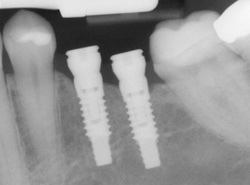

An implant is a synthetic tooth root in the shape of a post that is surgically placed into the jawbone. The “root” is usually made of titanium (the same material used in many replacement hips and knees), a metal that is well suited to pairing with human bone. A replacement tooth is then fixed to the post. The tooth can be either permanently attached or removable. Permanent teeth are more stable and feel more like natural teeth.

Implants are versatile. If you are only missing one tooth, one implant plus one replacement tooth will do the trick. If you are missing several teeth in a row, a few strategically placed implants can support a permanent bridge (a set of replacement teeth). Similarly, if you have lost all of your teeth, a full bridge or full denture can be permanently fixed in your mouth with a strategic number of implants.